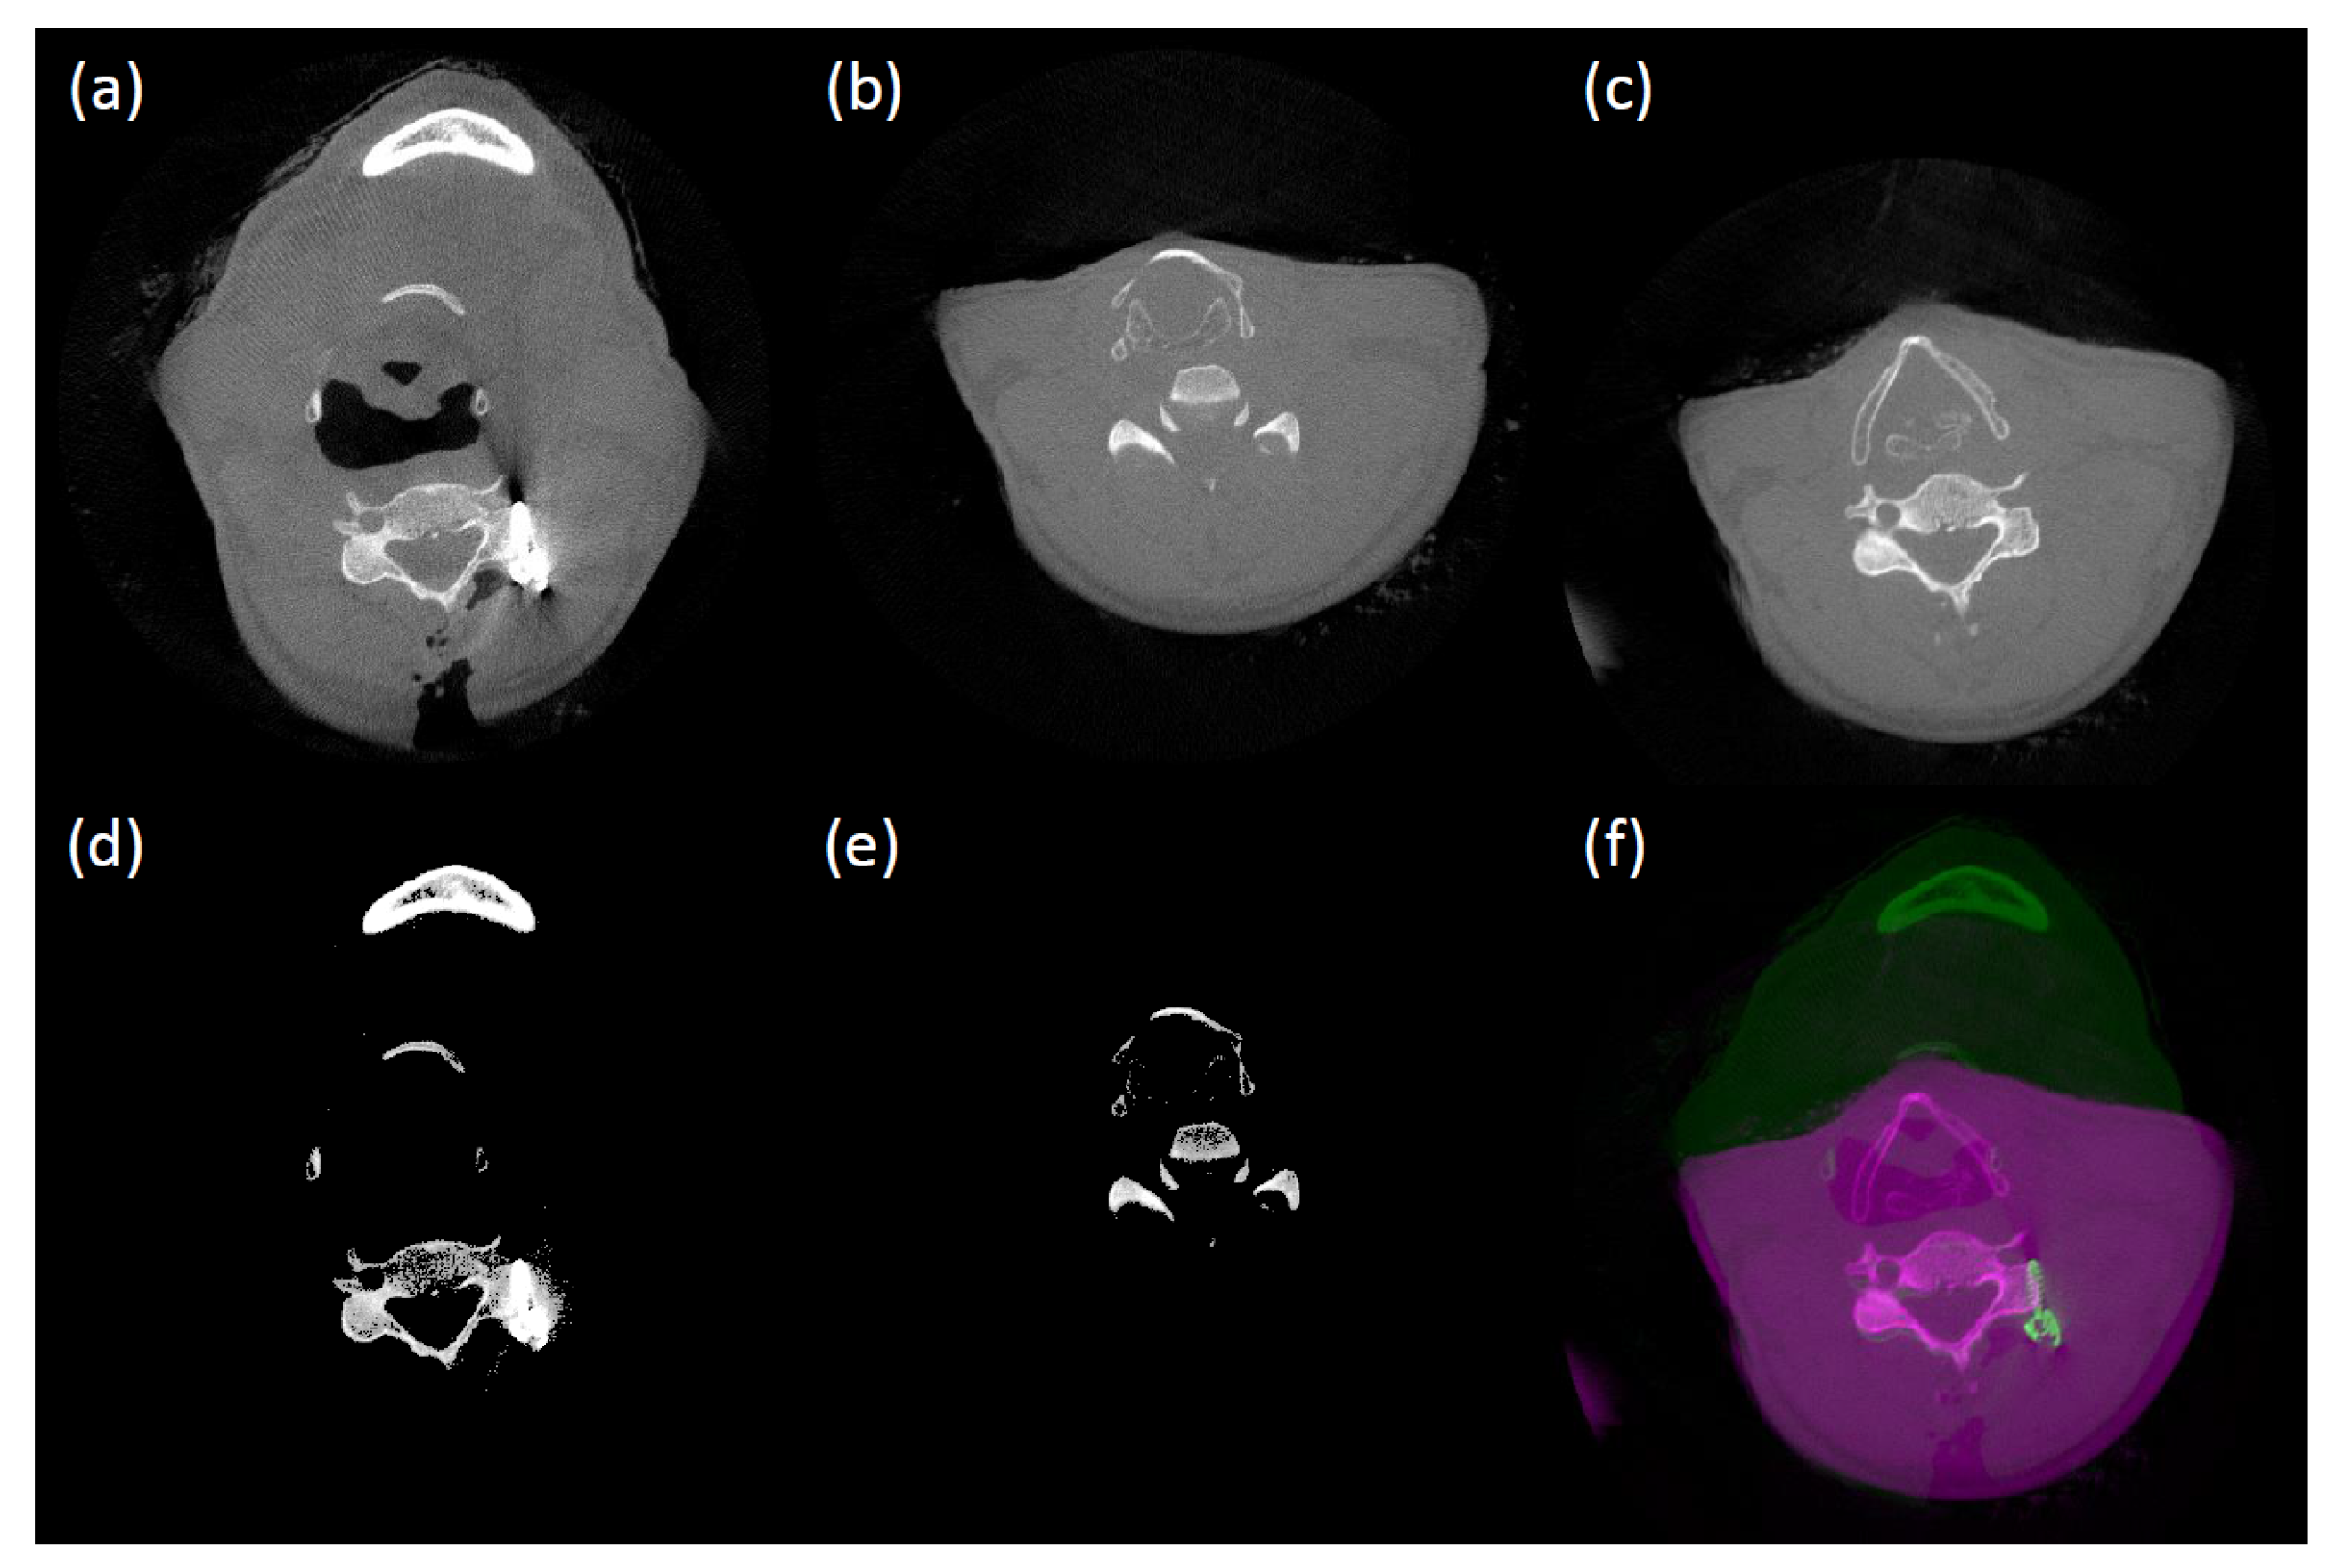

Instead, we align the two volumes and then find the set of matched prior profiles. The challenge in aligning two CT volumes taken at different times is that there can be large discrepancies in the soft internal structures (e.g., tissues). To resolve this problem, we first extract bone structures which are quite robust to deformation and also less contaminated by metal artifacts, in contrast to soft structures (see Figure 2 for a visualization). For the bone structure extraction, assuming there are only low and high density materials, we employ the balanced histogram thresholding (BHT) method [29]. Figure 3 shows two CT volumes obtained before and after surgery along with bone structures extracted using the BHT method. The prior volume is then rigidly registered to the uncorrected one by solving the following minimization problem:

We use a GPU-accelerated Hybrid-PSO (particle swarm optimization) algorithm to solve the minimization problem in Equation (4), which avoids a convergence to a local minima [30,31]. More specifically, in each generation, we randomly choose half of the particles and randomly adjust either a translation or rotation parameter with uniform probability. In every third generation, we pick half of the worst particles. The first half of these are replaced with completely new random values. Among the remainder, three-fifth of the particles are randomized as we do in each generation and the crossover is applied to the others. These types of randomization strategies have proven effective in finding the global solution in different optimization tasks [31,32]. A new generation is spawned until either there are no change in the best solution compared to previous one or it reaches the maximum number of generations pre-defined. Figure 3 shows an example of the rigid registration result.

Figure 3. Rigid CT volume registration: (a) uncorrected CT volume; (b) prior CT volume; (c) registered prior CT volume to (a); (d) extracted bone structures of (a); (e) extracted bone structures of (b); and (f) pseudo-colored overlap view of (a,c). Note that the presented CT slices, (a,b), initially show large discrepancy, even though they are sampled from same z-index before applying the registration.